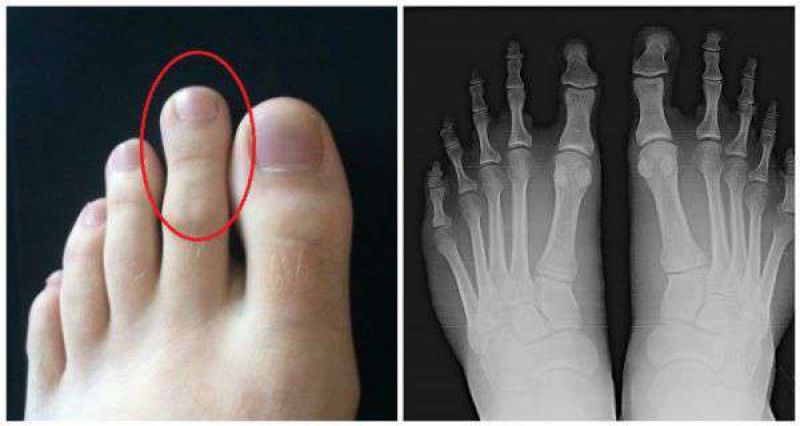

ਅਥਲੀਟ ਅਜਿਹੀ ਹੀ ਇਕ ਨੁਕਸਾਨਦਾਇਕ ਸਮੱਸਿਆ ਹੈ। ਅਕਸਰ ਪਲੇਟਫ਼ਾਰਮ ਅਤੇ ਪੈਂਸਿਲ ਹੀਲ ਕਾਰਨ ਅੰਗੂਠਾ ਸਿੱਧਾ ਹੋਣ ਦੀ ਬਜਾਏ ਟੇਡਾ ਹੋ ਜਾਂਦਾ ਹੈ ਅਤੇ ਜ਼ਿਆਦਾ ਦੇਰ ਤਕ ਇੱਕ ਹੀ ਹਾਲਤ 'ਚ ਰਹਿਣ ਨਾਲ ਉਸ 'ਤੇ ਦਵਾਅ ਪੈਂਦਾ ਹੈ ਜਿਸ ਨਾਲ ਪੈਰਾਂ ਦੀਆਂ ਮਾਸਪੇਸ਼ੀਆਂ ਅਤੇ ਅੰਗੂਠੇ ਦੀ ਹੱਡੀ 'ਤੇ ਬਹੁਤ ਮਾੜਾ ਪ੍ਰਭਾਵ ਪੈਂਦਾ ਹੈ। ਗ਼ਲਤ ਆਕਾਰ ਅਤੇ ਬਣਾਵਟ ਦੇ ਜੁਤੇ - ਚੱਪਲ ਤੁਹਾਡੀ ਅੱਡੀਆਂ ਅਤੇ ਉਨ੍ਹਾਂ ਦੀ ਮਾਸਪੇਸ਼ੀਆਂ ਨੂੰ ਪ੍ਰਭਾਵਤ ਕਰਦੇ ਹਨ। ਇਸ ਨਾਲ ਅੱਡੀਆਂ 'ਤੇ ਦਵਾਅ ਪੈਂਦਾ ਹੈ ਅਤੇ ਉੱਥੇ ਗੰਡਾਂ ਪੈਣ ਲਗਦੀਆਂ ਹਨ। ਦਸ ਦਈਏ ਕਿ ਪੈਰ ਦੀ ਲੰਬਾਈ ਵੀ ਅੱਡੀਆਂ 'ਤੇ ਹੀ ਨਿਰਭਰ ਹੁੰਦੀ ਹੈ। ਇਸ ਲਈ ਸਾਵਧਾਨੀ ਵਰਤਣ ਦੀ ਸਖ਼ਤ ਲੋੜ ਹੈ। ਤੁਹਾਡੇ ਜੁੱਤੇ - ਚੱਪਲਾਂ ਦੀ ਬਣਾਵਟ ਤੁਹਾਡੇ ਤਲਵਿਆਂ ਨੂੰ ਵੀ ਪ੍ਰਭਾਵਤ ਕਰਦੀ ਹੈ। ਇਨ੍ਹਾਂ ਤੋਂ ਤੁਹਾਡੇ ਤਲਵਿਆਂ ਵਿਚ ਖੱਡੇ ਜਾਂ ਫਿਰ ਦਾਗ਼ - ਧੱਬੇ ਦੀ ਸੰਭਾਵਨਾ ਵਧ ਜਾਂਦੀ ਹੈ। ਤਲਵਿਆਂ 'ਚ ਅਕੜਨ ਆਉਣ ਦਾ ਖ਼ਤਰਾ ਵੀ ਵਧ ਜਾਂਦਾ ਹੈ।